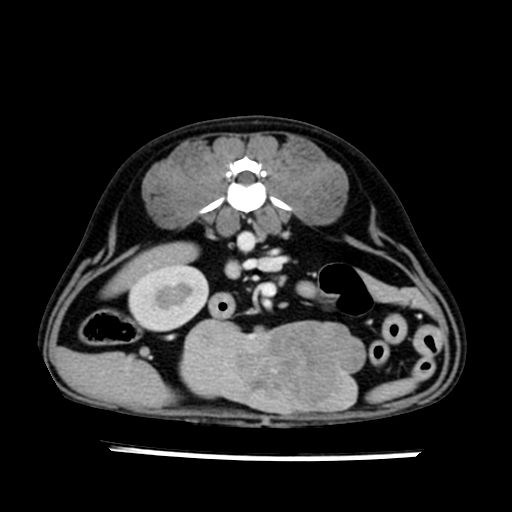

prescritto esame TAC

sequenza immagini limitata al fegato reni e surreni

le immagini ecografiche rispetto alla tac datano circa 7 mesi prima ,le surrenali sono normali nonostante il test acth sia risultato positivo .all’esame TAC dopo diversi mesi risultano aumentate armonicamente nel volume e si individua un forte sospetto di adenoma ipofisario .

sospetto adenoma ipofisario vs. meno probabilmente meningioma della base; intertiziopatia polmonare; lesione espansiva epatica, verosimilmente del lobo laterale sinistro, di sospetta natura neoplastica; lesioni spleniche di natura da definire; iperplasia/ipertrofia delle ghiandole surrenali, bilateralmente; vertebra di transizione del rachide toracico; tenosinovite cronica del muscolo bicipite brachiale di destra.